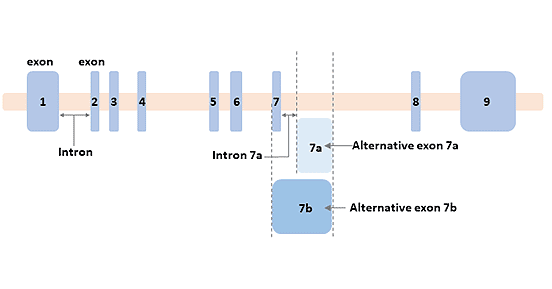

星形膠質細胞在大腦中含量豐富,是大腦 中最豐富的細胞類型,為神經元(包括神經遞質谷氨酸循環和營養因子釋放)提供結構和功能 支持,在神經生理活動、神經組織再生及免疫、多種神經疾病的發病中發揮重要作用。

作為星形膠質細胞內的主要骨架蛋白, GFAP在細胞核和細胞膜之間形成連接,參與細胞內細胞骨架重組、細胞黏附、維持腦內髓鞘 形成和神經元的結構以及作為細胞信號參與轉導通路等[8] [9],還參與細胞遷 移、運動和有絲分裂。膠質纖維酸性蛋白具有維護星形膠質細胞形態穩定、參與血腦屏障形 成、調節突觸功能等多種生物學功能。

6.4 星形膠質細胞-神經元相互作用

星形膠質細胞參與了神經元的多種功能, 包括突觸的形成和可塑性,能量和氧化還原的代謝,以及神經遞質和離子的突觸穩態停滯。

圖3 星形膠質細胞的功能

6.5 血腦屏障和髓鞘形成

血腦屏障(BBB)由毛細血管內皮細胞形成 ,周圍被基底層和血管周星形膠質細胞的特定末端包圍。